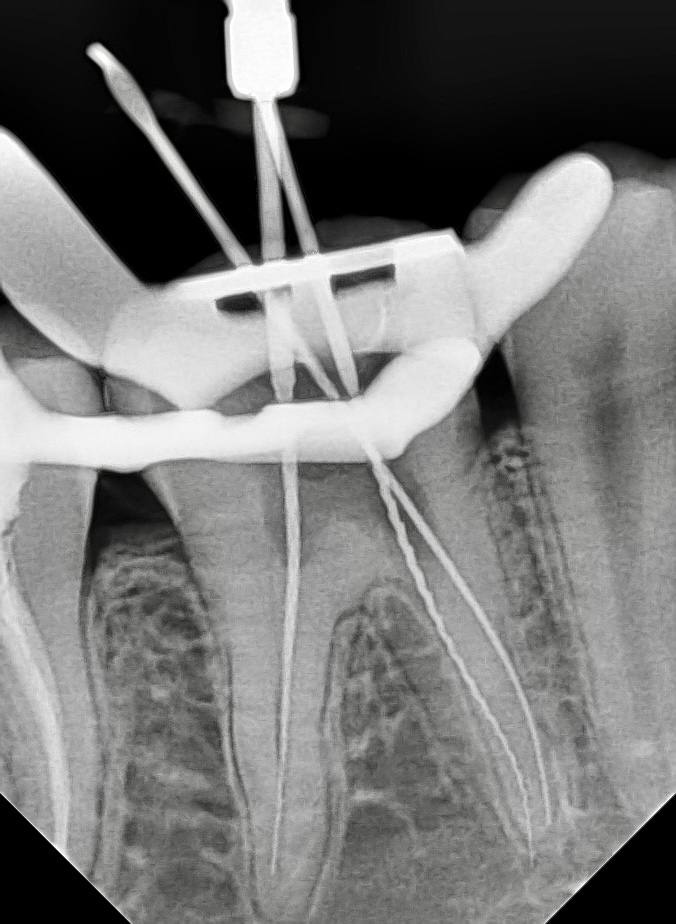

- После появляется намеков на ход канала - вкручивание моторным файлом

- После опережение рабочей длины и расширение корневых каналов файла Soco plus до 30.04